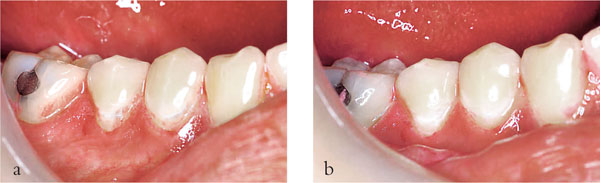

For a patient with new and secondary caries (Fig 1-5a,b) it is important that treatment is carried out in phases. The first phase should address pain and other immediate problems. Thereafter, care should be aimed at prevention. This stage of treatment should include stabilisation of the lesions and protection with temporary and transitional restorations. This is necessary to ensure that extensive lesions do not progress during the preventive phase of treatment. It also allows a stepwise approach to caries removal.

Fig 1-5 (a,b) A left bitewing radiograph of an 18-year-old patient (a), and four years later (b). This demonstrates that caries risk can change and the dentist should always be vigilant and continually assess risk. This patient’s initial treatment should be pain relief, followed by a stabilisation phase and prevention. Indirect restorations should not be considered until successful prevention has been instituted and caries risk has been controlled.